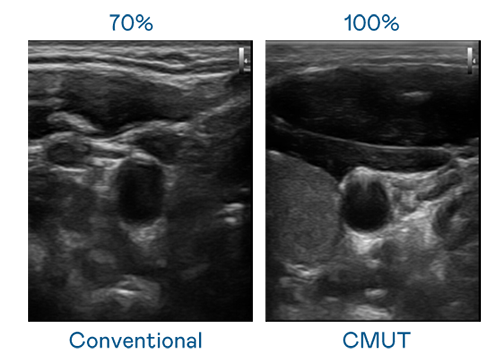

CMUT 技术是一种用电容式微机电元件来产生超音波讯号的技术。与传统 PZT 压电式技术相比,CMUT 频宽增加 30%,更宽频的超音波讯号让影像解析度大幅提升,是实现高影像品质医疗超音波扫描、促进精准医疗发展的关键技术。

超音波影像的解析度高低,首先取决于探头能发出的讯号频宽。壹号娱乐 CMUT 可提供高清晰的超音波讯号,提供高频宽、高灵敏度、影像纹理细节更高的超音波影像,协助医护人员缩短影像判读时间及利用精准的医疗影像进行诊断。